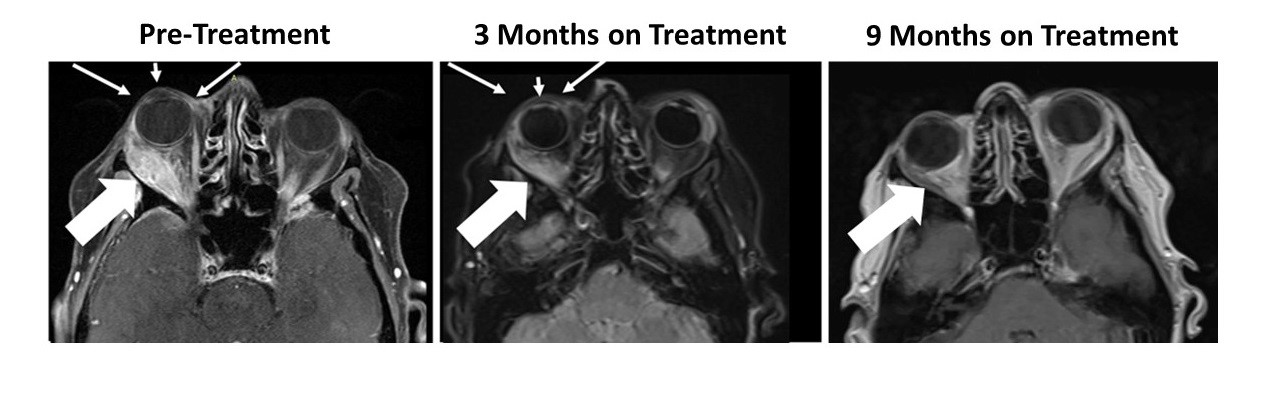

The patient had a large right orbital lesion (behind the right eye) and a right temporal lobe lesion (in the right side of the brain). The temporal lobe lesion is no longer detectable, while the orbital lesion has continued to shrink markedly (see figure showing resolution of proptosis post treatment (small arrows) with reduction in tumor indicated by the large arrows). In addition, her tumor markers (blood tests that correlate with the amount of tumor in the body) have markedly decreased from her pre-treatment levels.

Figure 1: Responder Images – Bria-IMT™ Regimen